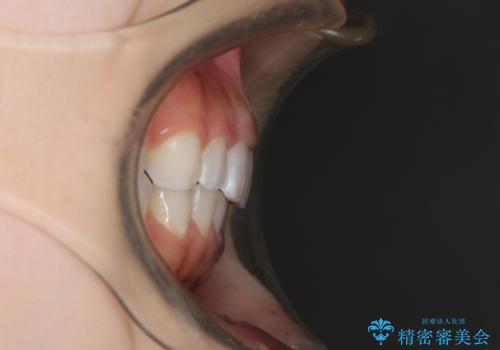

デコボコと深い咬み合わせの改善 インビザラインによる矯正治療

- 口元のデコボコと深い咬み合わせ(ディープバイト)を気にして来院された患者様です。

インビザラインによる上下歯列の拡大と、IPR(歯と歯の間を削る)にるスペースの獲得により、口元のデコボコとディープバイトを改善することとしました。